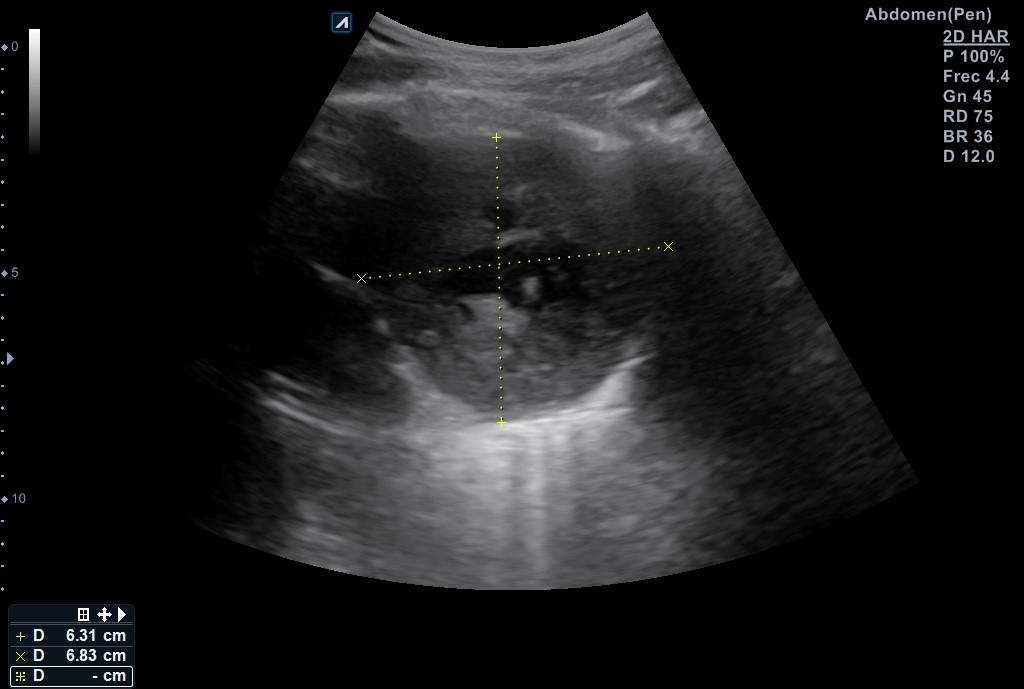

Se realiza ecografía pulmonar donde se identifica una masa anterior en el vértice del pulmón derecho, de aspecto sólido con centro necrótico de unos 7-8 cm de diámetro en anteroposterior y transversal, sin poder precisar diámetro longitudinal por interposición de costillas, clavícula y esternón.

Masa en mediastino anterior izquierdo. Diagnóstico diferencial: linfoma vs timoma vs neoplasia pulmonar. Se contacta con Medicina Interna para estudio urgente, donde le solicitan un TC cuello-tórax con contraste IV (resultados: masa en vértice medial pulmón izquierdo, de contorno bien definido y abundante necrosis) Mide 12,5 x 5,3 x 7,5 cm.